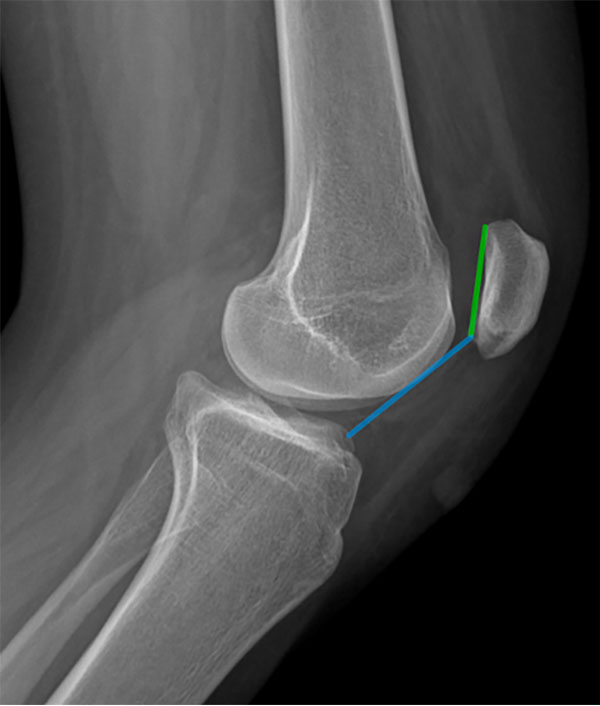

Se han descripto múltiples métodos para cuantificar la altura patelar en radiografías. En la actualidad, el índice más utilizado en la literatura es el de Caton-Deschamps (ICD)2,16 (fig. 2). Este consiste en el cálculo de la relación entre la distancia desde el punto inferior de la superficie articular de la rótula hasta la meseta tibial anterosuperior (AT) y la longitud de la superficie articular de la rótula (AP). Este índice presenta el beneficio de no verse afectado con las osteotomías de distalización de la tuberosidad anterior de la tibia (TAT) permitiendo, así, evaluar la corrección postoperatoria de la altura patelar. Valores >1.2 son considerados como patela alta.4

Actualmente, no ha sido demostrada una clara concordancia entre las medidas de la altura patelar en radiografías, TC y RM, estas últimas se ven afectadas por el grado de flexión de la rodilla, la contracción del cuádriceps y la modalidad de imagen, por lo que deben emplearse con cautela.

Figura 2: Índice de Caton-Deschamps (ICD). Calculado como la relación entre la distancia entre la parte más anterior de la superficie articular tibial (línea azul) y el largo de la superficie articular patelar (línea verde).